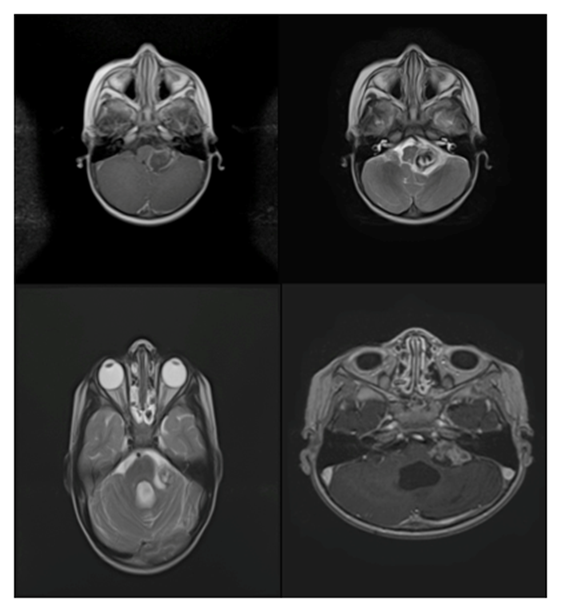

A 15-year-old male patient who consulted for a 5-month headache that increased with valsalva maneuvers, photophobia, located in the occipital region. The physical examination revealed an ataxic syndrome. Brain tomography and MRI imaging showed an infratentorial brain tumor in the posterior fossa, compromising the IV ventricle, approximately 4.5 x 3 cm, with heterogeneous enhancement with Gadolinium, the lesion expands and obliterates the IV ventricle, extending through the holes towards the area of the right pontocerebellar angle; produces supratentorial obstructive hydrocephalus with transependimary exudation; no spinal spread was found (Figure 2a). The tumor was completely removed by sub-occipital craniectomy. Postoperative control resonance showed recession of the right cerebellar amygdala, post-operative changes without abnormal contrast uptake, and no residual tumor lesion was found. The pathological diagnosis was anaplastic grade III ependymoma, monomorphic cells of round and oval nuclei were observed, forming perivascular pseudorosettes, with frequent mitosis and necrosis (Figure 1). Subsequently, radiotherapy was performed with IMRT with a total dose of 5400 CGY. The patient finished the treatment without neurological deficit. The patient remains in follow-up with a stable condition.

Figure 2a Radiology: Anaplastic Ependymomas.

Patient no. 2. Lesion with cystic and solid component, presenting compromise of the fourth ventricle, the uptake is heterogenous with nodular component.